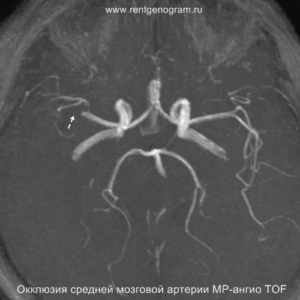

На остром этапе (Т2, Т1 и Flair могут сохранять нормальные результаты), на МРА можно обнаружить окклюзию артерии (при атеротромбоэмболическом и кардиоэмболическом механизмах), что будет выглядеть как отсутствие МР-сигнала от ведущей артерии (ВСА или СМА). Контрастное усиление на МРТ в остром этапе не приводит к накоплению контраста в области повреждения.

В течение острого этапа на МРТ и КТ выявляются все морфологические признаки ишемического инсульта. Область острого ишемического инфаркта визуализируется как зона ↑Т2, ↑Flair, ↑DWI и ↓Т1 ↓ADC. Можно обнаружить тромб в артерии. На КТ в остром этапе также чётко дифференцируется поражённая область, представляющая собой участок с потерей дифференциации мозговых структур и снижением их плотности. Контрастирование в остром периоде не показывает патологических участков с накоплением контраста.